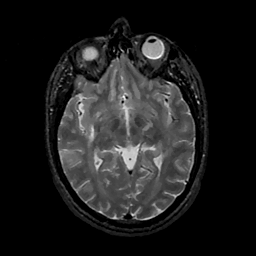

MR Study #11, May 5, 1991 -- Slice #23